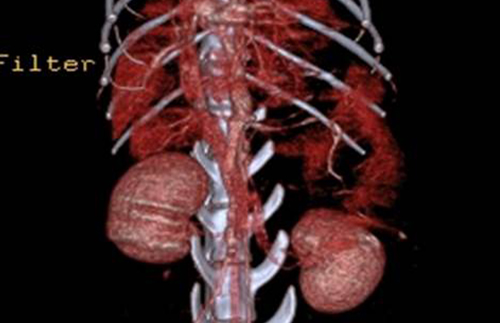

- 외과센터 소개 - 외과수술 종류 - 주요수술 안내